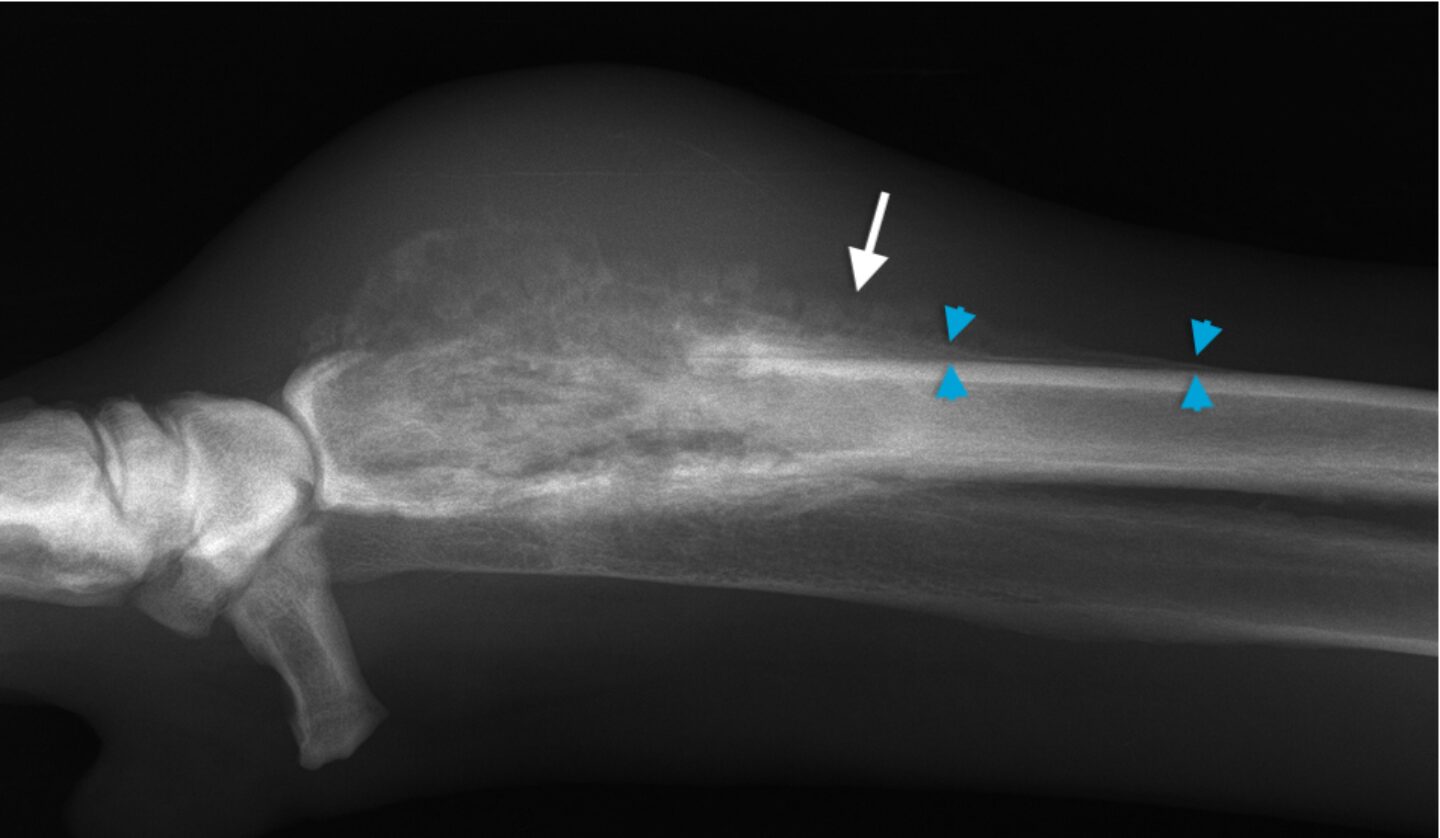

Die Einteilung von Knochenveränderungen erfolgt basierend auf ihrem röntgenologischen Erscheinungsbild in aggressive, intermediäre und nicht-aggressive Läsionen. Neben dem Erscheinungsbild von Osteolyse und Osteogenese, bestimmen die Länge der Übergangszone und der zeitliche Verlauf über die Klassifikation. Die verschiedenen Formen der Osteolysen sind in Tabelle 1 aufge